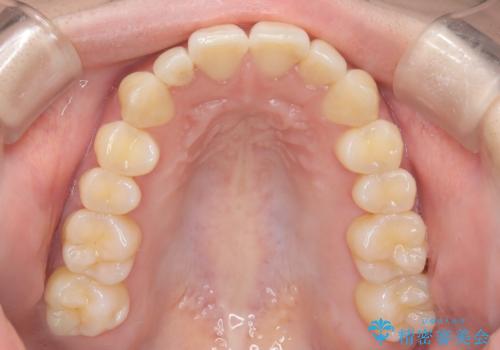

【インビザライン】反対咬合を治したい

- 前歯の反対咬合を主訴に来院されました。

インビザラインにて歯列弓の拡大により叢生の改善を行うことができ、患者様にも満足していただました。

前歯の反対咬合は歯牙への負担も大きくできるだけ早期に治療を行うことを推奨しています。